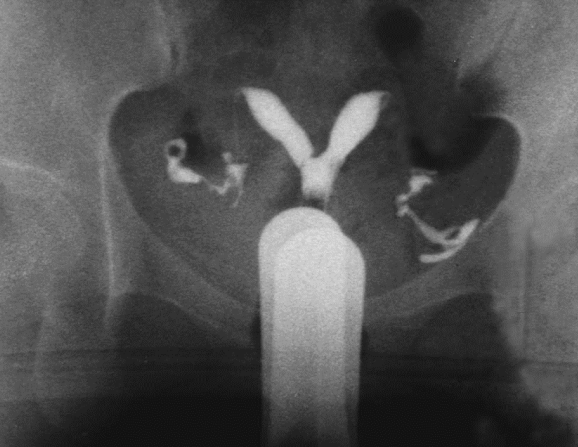

双子宫碘油造影(双子宫双宫颈)

(五)双角子宫(bicornuate uterus)

根据宫角在宫底水平融合不全的程度分为完全双角子宫和不全双角子宫。一般无症状。有时双角子宫月经量较多并伴有程度不等的痛经。检查可扪及宫底部有凹陷。超声检查、磁共振显像和子宫输卵管碘油造影有助于诊断。一般不予处理。若双角子宫出现反复流产时,可行子宫整形术。

双角子宫二维超声碘油造影

完全纵隔子宫碘油造影

不完全纵隔子宫碘油造影

一般无症状。临床上主要表现为影响生育期妇女的妊娠结局,包括反复流产、早产、胎膜早破等表现,其中以反复流产为最常见。经阴道超声检查是目前最常用的诊断方法,表现为两个内膜回声区域,子宫底部无明显凹陷切迹。子宫输卵管碘油造影(HSG)有助于了解宫腔形态,评估双侧输卵管通畅与否。宫腹腔镜联合检查是诊断纵隔子宫的“金标准”方法。